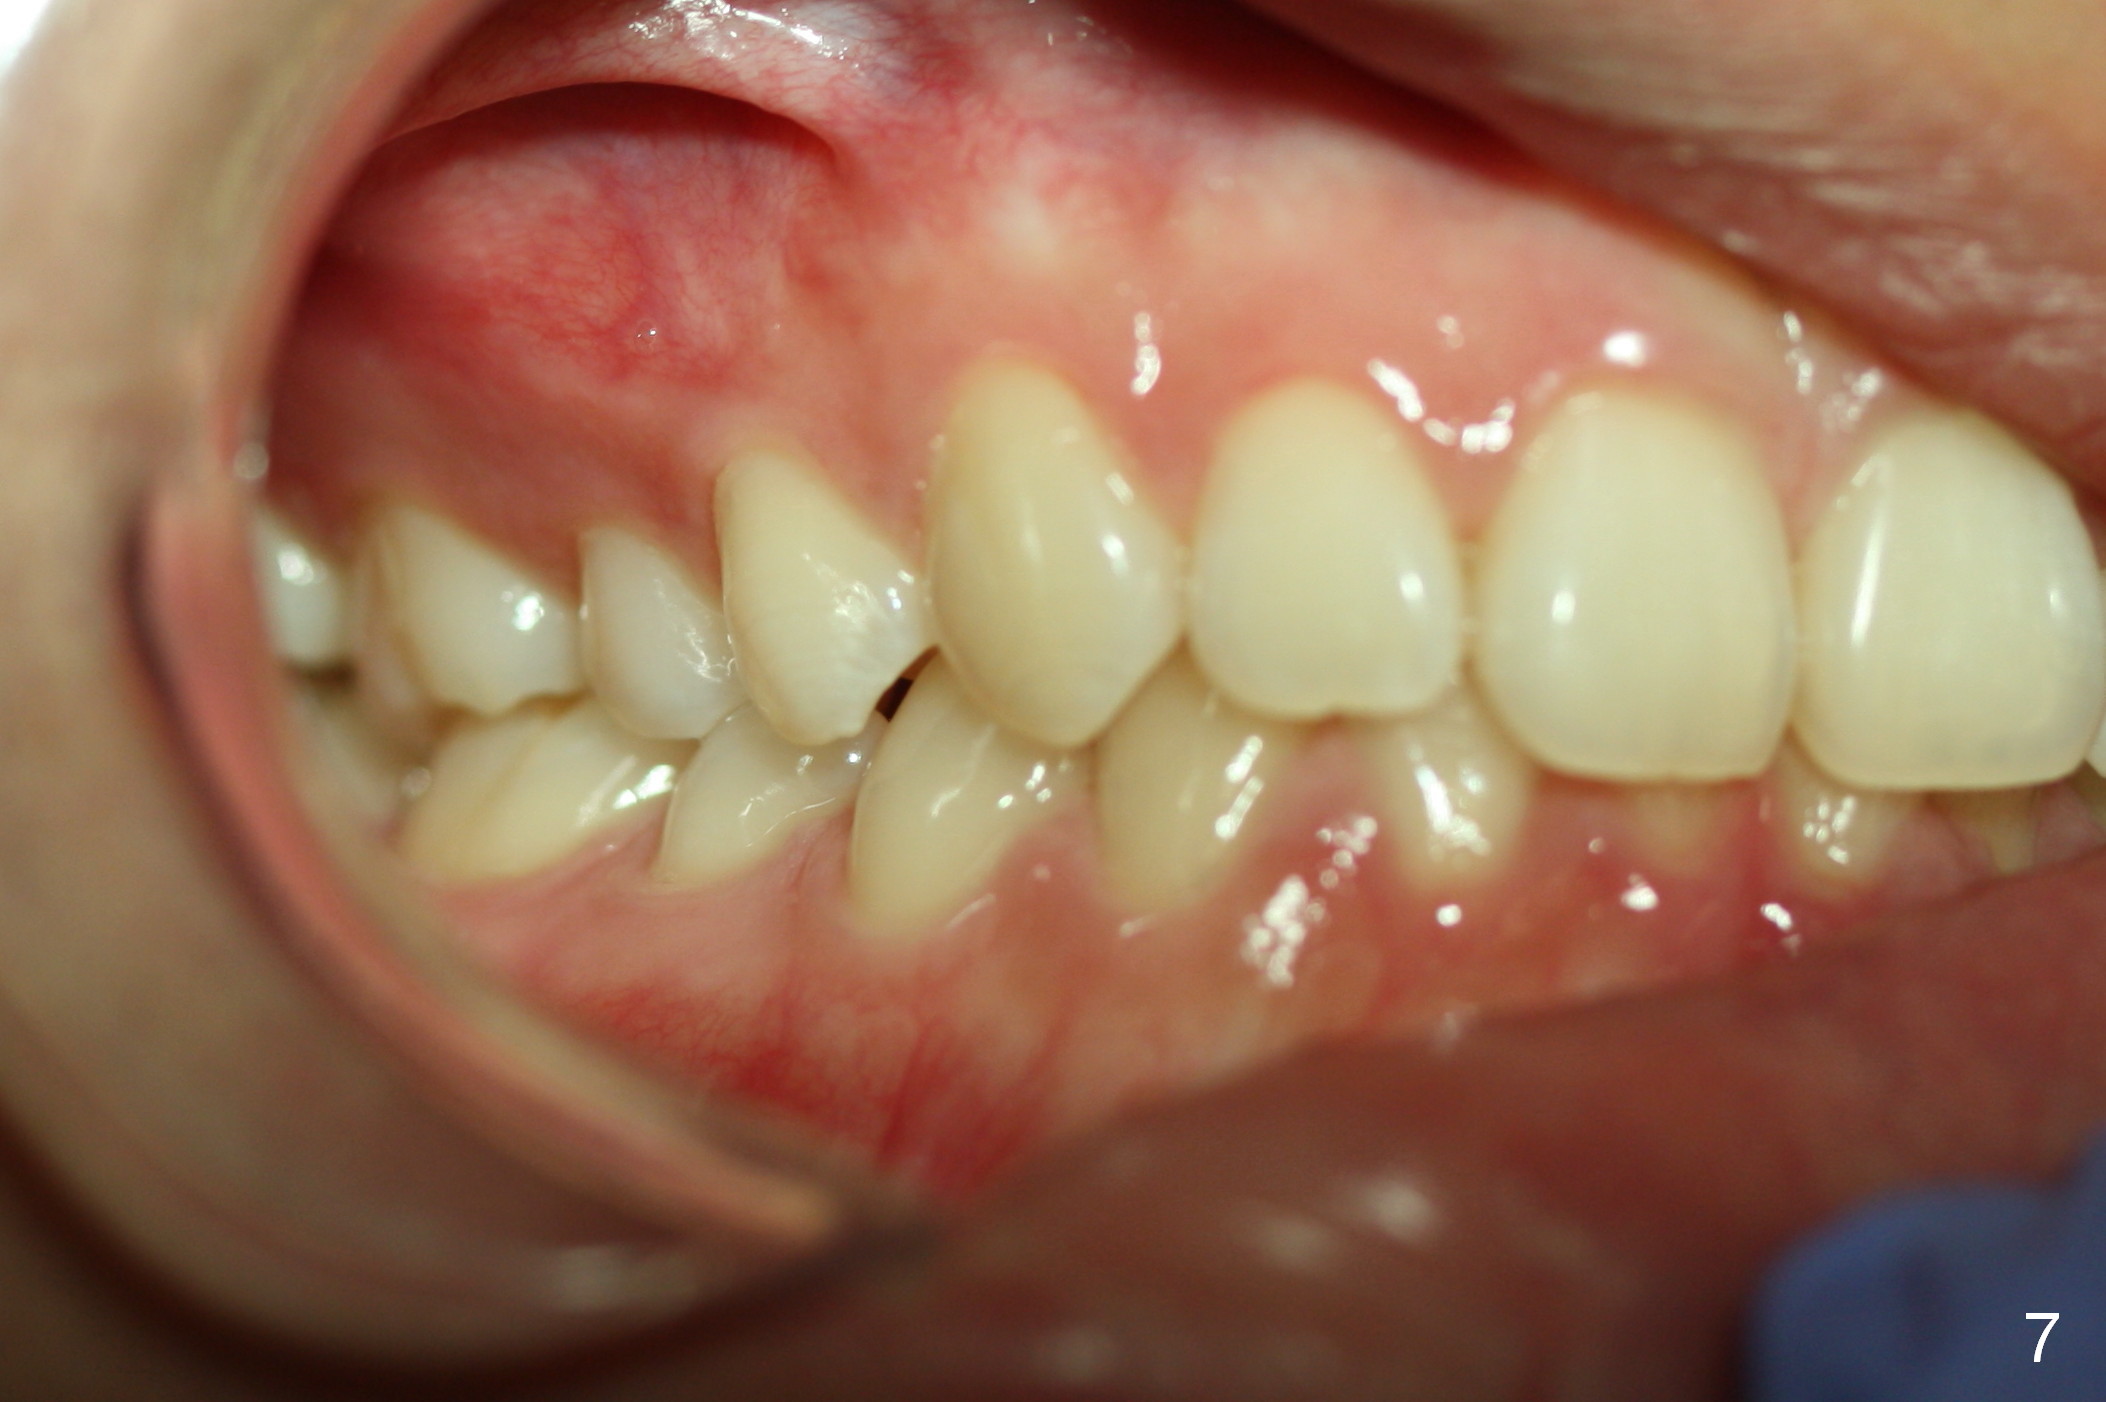

To show the posterior occlusion directly, use the smaller single cheek retractor to retract the corner of the mouth as posterior as possible. For better exposure, ask the patient to hold a mouth mirror lightly at the other corner of the mouth. The camera should be also positioned posteriorly with focus on the region between the canine (mainly) and the 1st molar (as compared to Fig.7 and 9).

To take the anterior view of the occlusion, let the patient turn the head slightly toward you. The camera frame should be parallel to the imaginary occlusal line. When the photo is not straight (Fig.8), it appears that we are unable to set the teeth straight, either.

Jessica is a 15-year-old Chinese. She cares about her upper central incisors and the upper left canine (rotation). Place rotation wedges as early as possible and overcorrect the rotation.